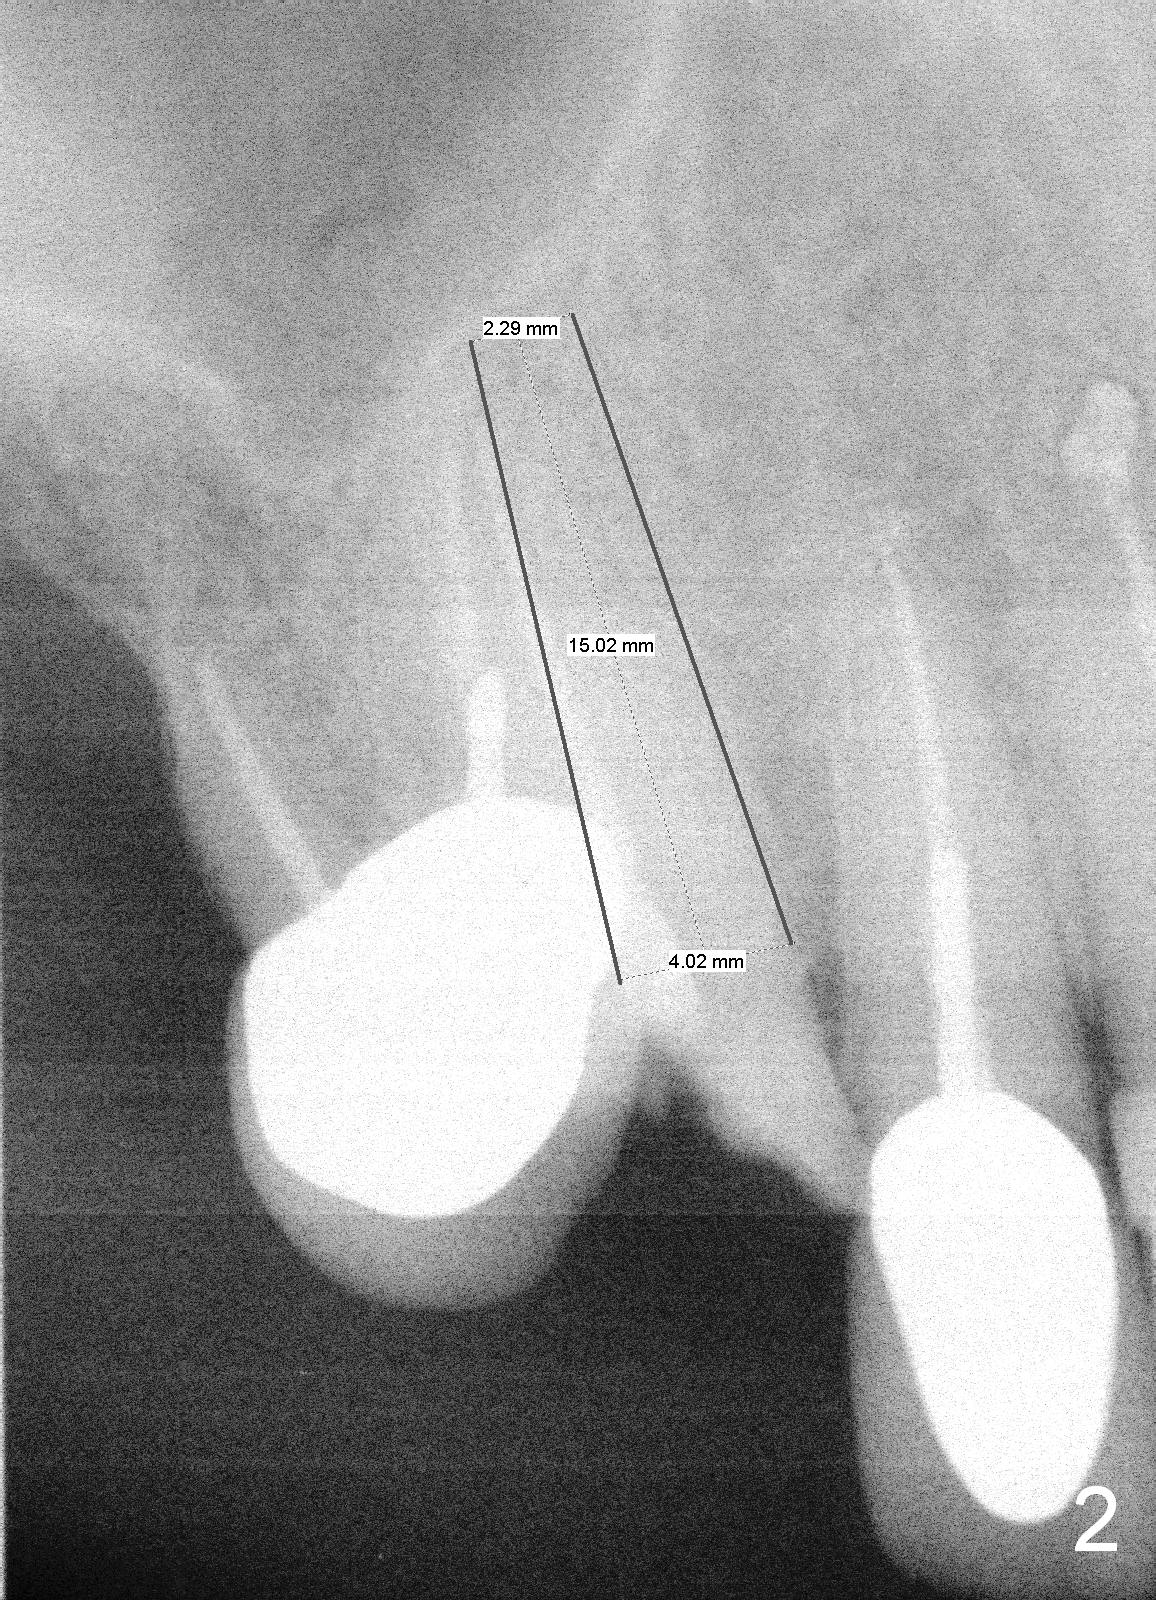

The tooth #6 of a 70-year-old man (TF) fractures subgingival (Fig.1) before final upper left implant restorations. A 15 mm or longer UF implant (Fig.2) seems to be appropriate for the site immediately after extraction (socket treated with Clindamycin).